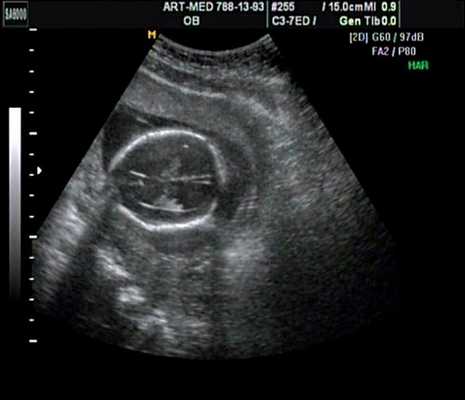

Антенатально при равных величинах давления в желудочках сердца и в предсердиях объемной перегрузки не возникает. В связи с этим ни один из эхокардиографических гемодинамических признаков, используемых у детей и взрослых, не выявляется у плода. К эхокардиографическим проявлениям порока антенатально относится только прямой признак - перерыв ультразвукового луча в области дефекта. Размеры сердца, соотношение размеров желудочков сердца не отличаются от нормы (рис. 5).

Рис. 5. Четырехкамерное сечение сердца плода. Стрелкой указан первичный дефект межпредсердной перегородки (АVS).